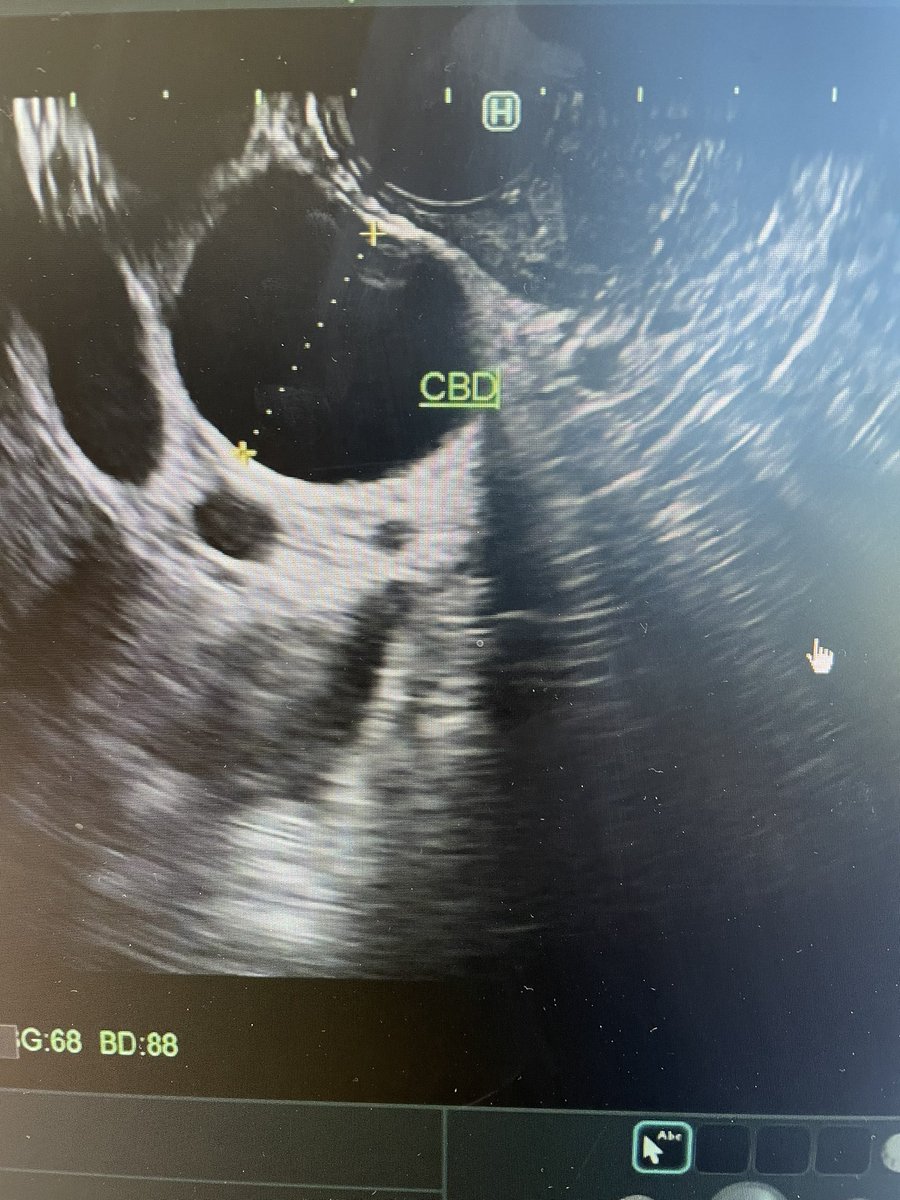

@Bashar_Qumseya Cholangitis with cbd wall thickening ? Stone impacted or papillary stenosis